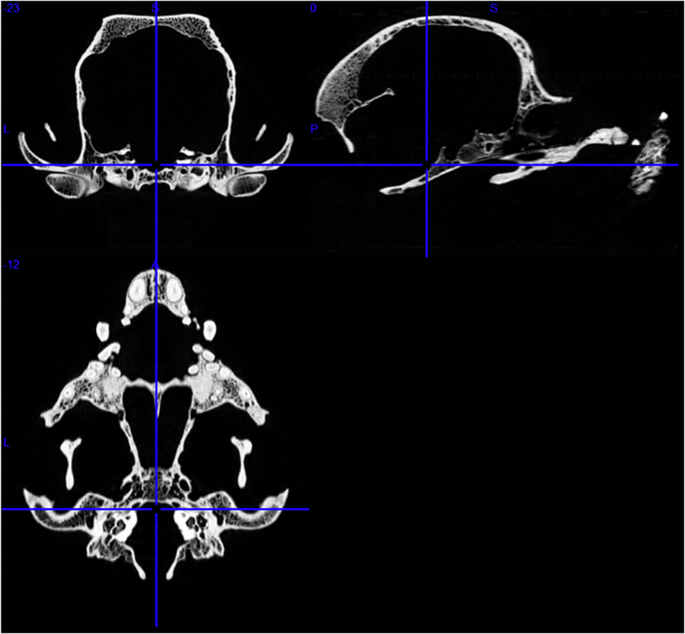

Image: Skull of a Boston terrier on a CT image series. First row: transverse and sagittal views. Second row: dorsal view. Credit: Kálmán Czeibert